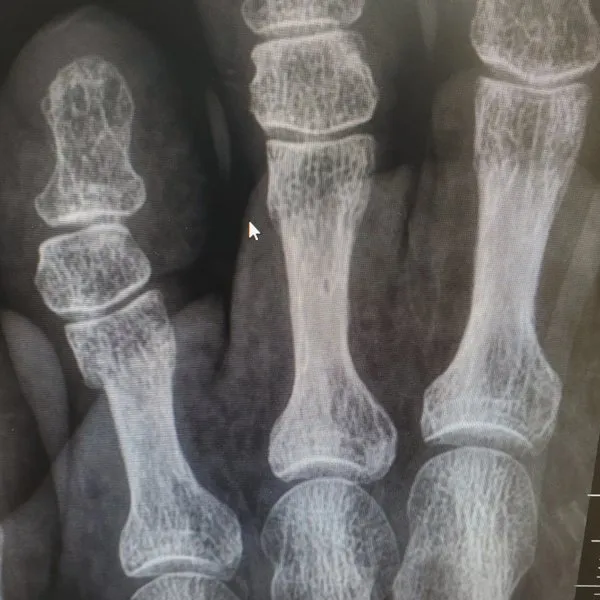

See What's Going on Inside Our Podiatrist's Office

With 32 years of experience, Dr. Daniel Brandwein DPM, PA, FACFAS is your trusted choice for podiatric care in the Pompano Beach, FL area. Take a look at the photos below to see what's happening inside our locally and family owned clinic. To find out how we can help with your foot care needs, please contact us today.